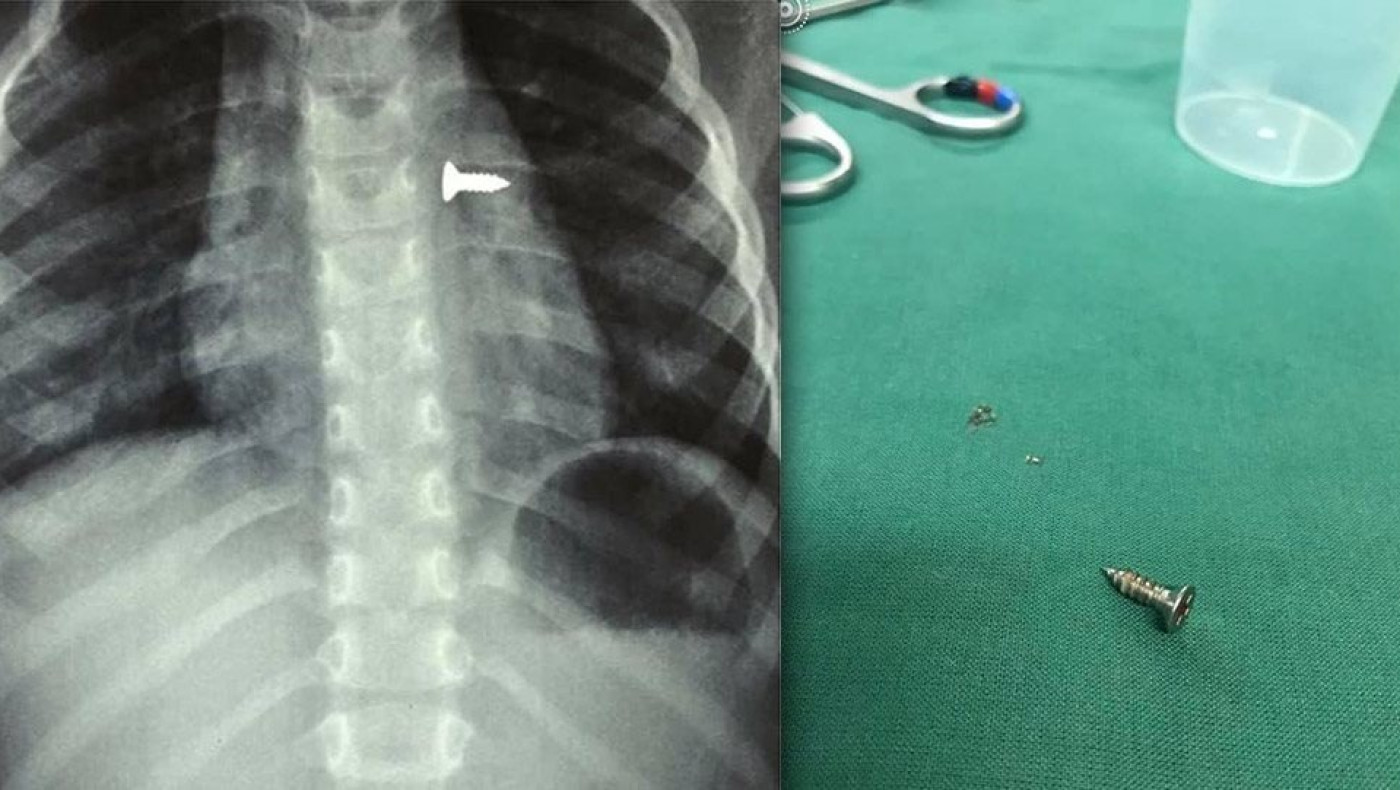

Σοκάρουν οι ακτινογραφίες από ένα κοριτσάκι στην Κρήτη που κατάπιε βίδα, η οποία κατέληξε στον αριστερό του πνεύμονα.

Αμέσως έβγαλε ακτινογραφίες, που έδειξαν πως η βίδα βρισκόταν στον αριστερό του πνεύμονα.

Οι γιατροί οδήγησαν το κορίτσι στο χειρουργείο και μετά από αρκετή ώρα κατάφεραν να αφαιρέσουν την βίδα.

Ο κ. Προκοπάκης σε ανάρτησή του στα social media ανέφερε: «Πολύ επείγον χειρουργείο! Πριν από λίγο. Αφαίρεση βίδας από αριστερό βρογχικό δέντρο τρίχρονου κοριτσιού. Πολύ επικίνδυνο…».